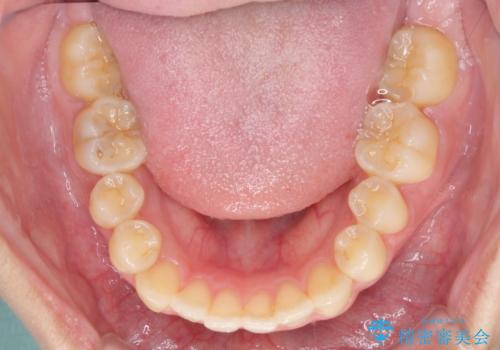

- 前歯のクロスバイトを気にして来院され患者様です。

定期的に日本には帰国するものの、日ごろは海外でお仕事をされているとのことで、インビザラインによる治療を希望されました。

トラブルが起こった時に対応ができない、来院を帰国のタイミングに合わせなければならないため治療が長期化するなど困難はありますが、ワイヤー矯正と比べると治療を進めやすいといったメリットがあるので、インビザラインにて矯正治療を行うこととしました。